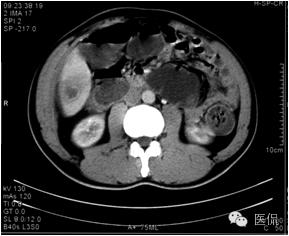

延迟期密度略有下降,但仍有强化,形态不规则。

手术病理诊断:

肝炎性假瘤,侵及周围结肠和腹壁,浸润组织有水肿,粘连。